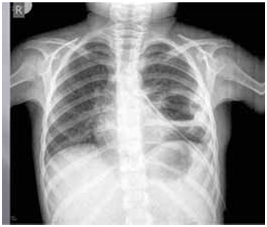

After discharge, all patients were treated with X-ray after 6 months of primary therapy. The criteria for radiological improvement were the loss of shaded cysts, and the resorption of postoperative pericystic inflammation and pleural reaction (Figure 12­–15).

Figure 15 X-ray finding after 6 months loss of shaded cyst and resorption of pericystic inflammation and pleural reactions.

Of the 80 patients treated in this study, we did not have a single case of relapse. Considering the large number of complicated, gigantic and multiple cleaners in both groups, we consider this result satisfactory. The literature published a recurrence rate of 2-12% while Sayir and associates had a recurrence rate of 1.4%.36 We further analyzed the finding of a control chest X-ray of the lung image 6 months after surgery. The success of the procedure was characterized by radiological improvement after 6 months. Radiological improvement was characterized by absence of atelectasis, loss of shadow operated cysts and resorption of postoperative cystic inflammation.

Based on the analyzed data of radiological recording in the investigated group, no subjects with lung atelectasis were recorded after surgery, while in the control group this complication occurred in 7 subjects. In the examined group, there was a disappearance of shadow of operable cyst in 31 subjects, while in the control group there were 20 respondents with shadow disappearing after 6 months. In the investigated group, there was a resorption of postoperative inflammation in 37 subjects, while in the control group there were 27 subjects who recorded resorption of postoperative pericystic inflammation. Following three radiological parameters, 6 months after surgery: the presence of atelectasis, the disappearance of shadow-operated cysts, and the resorption of postoperative periclinic inflammation, we concluded that the regression of radiological changes was significantly more pronounced in the test (capitonnage) compared to the control group (non-capitonnage).